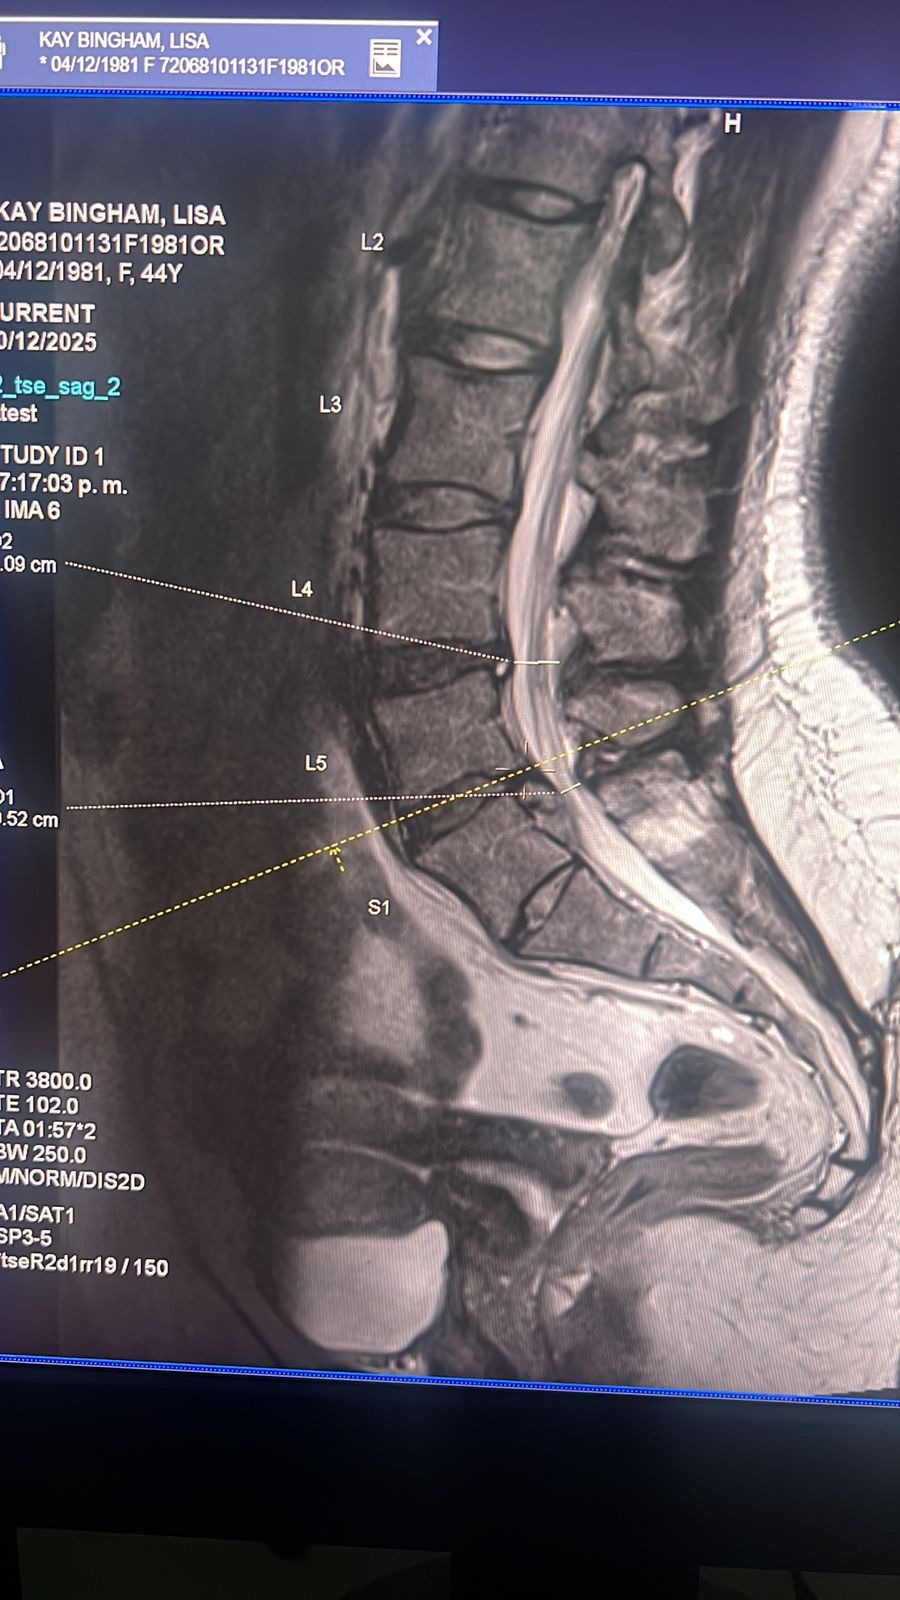

UPDATE: Hernia in spinal column was successfully removed, she is recovering and will need 8 weeks of therapy. We are feeling very blessed and she is happy to be home and very thankful to you all who have been following her story, donated and love her.

My daughter, Lisa Bingham, a divorced mother of 3 boys has been providing for her children with miniscule assistance from her ex husband. She recently moved to a large city where she could make more money to bring her youngest two children to join herself and her oldest (occuring this summer). About a month ago she started experiencing numbness and severe pain in her right leg. After meeting with her general physician, two surgeons and physiotherapist, she received word that 2 of the disc's would respond to therapy, however one area has a hernia that requires surgery, her surgery is scheduled and Lisa's has a medical coverage that is a workers medical insurance. Many people opt to go outside of the system for fear of being maimed or killed by inadequate providers, which frequently happens. Here is why we are sharing this. Lisa has received an estimate for her medical expenses from her separate MetLife insurance, which is posted here. Her surgeon had stated that it will be 500,000 pesos minimally, which is 30,000 US dollars. We know this is a tough time of year to request help, but please help with whatever you can, thank you in advance for your blessing.